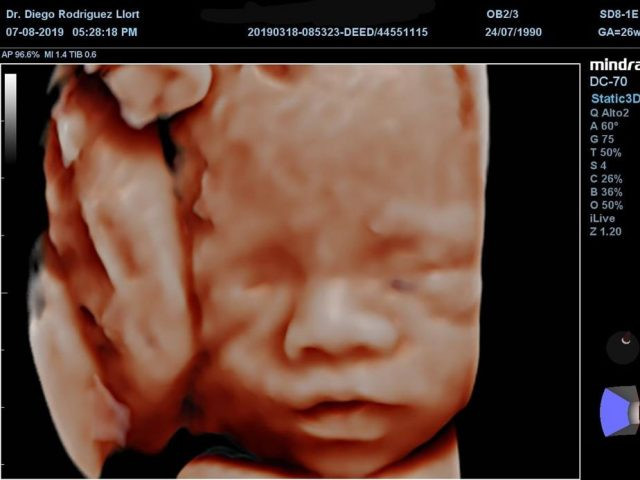

• Ultrasonido 3D y 4D: Las ecografías en tres dimensiones y cuatro dimensiones permiten ver de forma más clara al bebé, otorgándole volumen y movilidad en el 4D.

• Ultrasonido 5D: La ecografía 5D es capaz de realizar una reconstrucción más definida y realista del feto. La nueva generación de ecógrafos de alta resolución incrementa de manera decisiva la capacidad diagnóstica y la detección de malformaciones fetales.